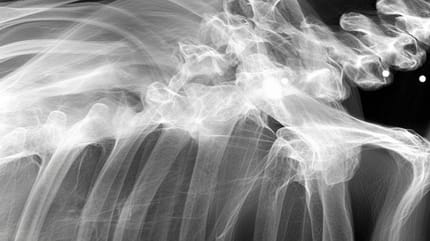

Une radio de chien

Mais quelques années après cette adoption très réussie, le maître de Momo a eu une bien mauvaise surprise en se rendant chez le vétérinaire pour une simple radio car sa chienne commençait à avoir du mal à se déplacer. Rapidement, le silence s’est installé dans le cabinet et le vétérinaire a pris son temps pour expliquer que la chienne avait sans doute vécu un passé très compliqué, fait de violence. En effet, la radio a révélé qu’elle avait probablement été utilisée pour de la reproduction en masse. Mais ce n’est pas tout. La chienne, qui souffrait aussi d'arthrite et de dysplasie de la hanche,  cachait un autre secret.

Rapidement, le vétérinaire a aussi constaté que la chienne avait été criblée de balles. Une des balles était passée tout près de sa colonne vertébrale. Mais fort heureusement, aucune de ces balles n’a réellement eu de conséquence sur la vie de cette chienne qui vit aujourd’hui tout ce dont elle a toujours rêvé, comme l'indiquent nos confrères de Newsweek.